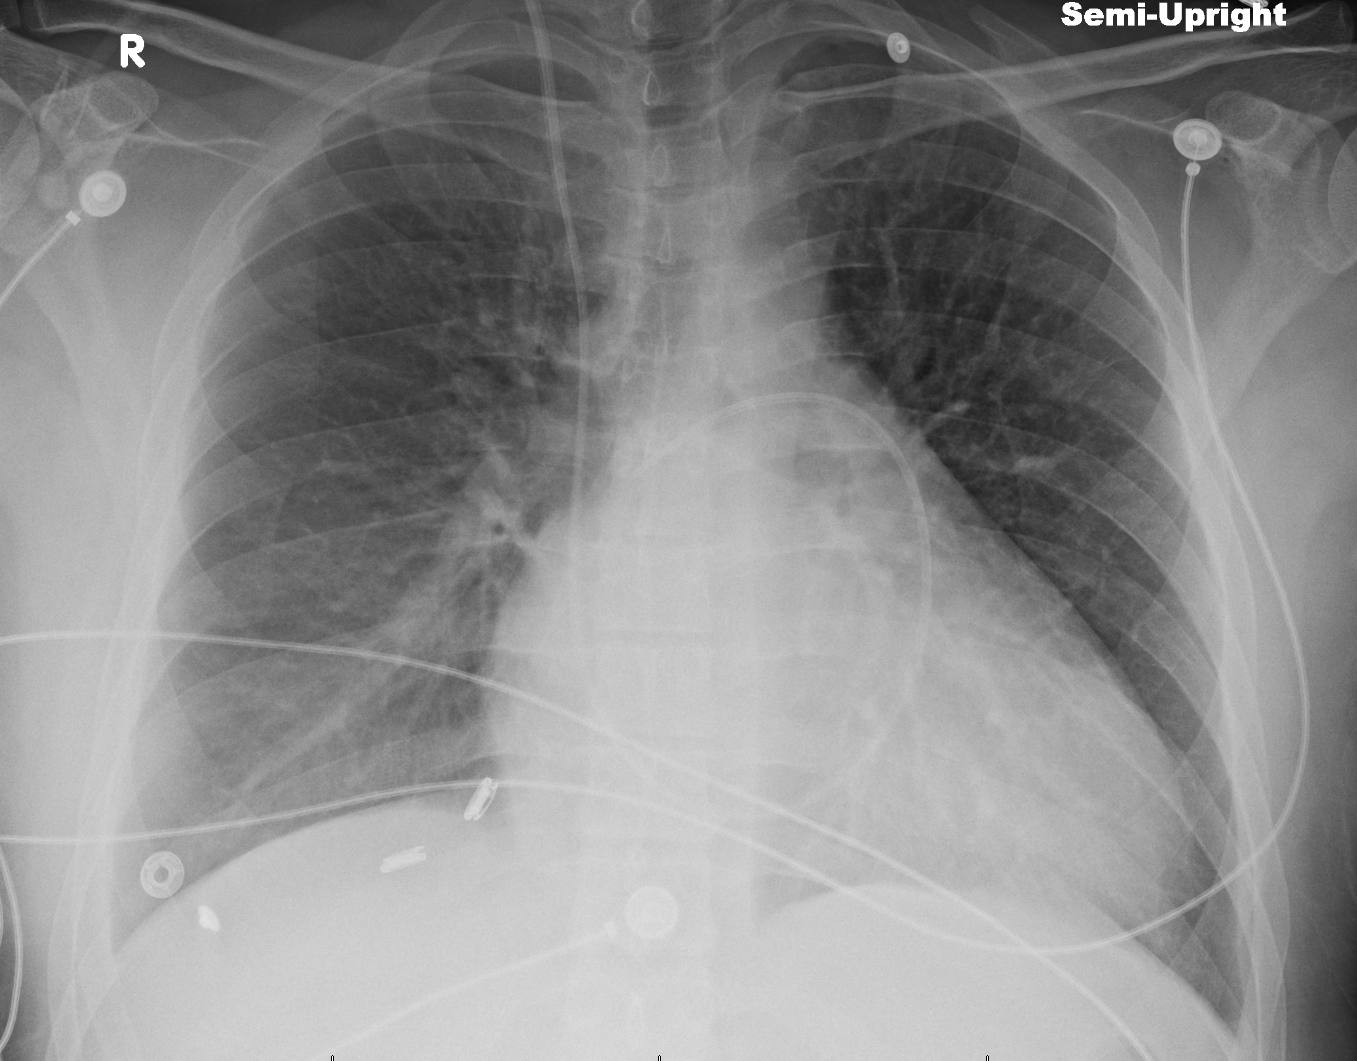

Congestive Heart Failure Chest X Ray Chest X Ray To Diagnose Heart Failure They could be taken in the health care professional’s office or in a separate radiology lab. Because the outlines of the large vessels near your. Alveolar edema with perihilar consolidations and air bronchograms (yellow arrows); A displaced cardiac apex, a third heart sound, and chest radiography findings of venous congestion or interstitial edema are useful in identifying heart failure. Blood. Chest X Ray To Diagnose Heart Failure.

Patient's chest xray after myocardial infarction and 3 codes shows Chest X Ray To Diagnose Heart Failure The following signs indicate heart failure: Blood tests can help diagnose diseases that can affect the. They could be taken in the health care professional’s office or in a separate radiology lab. Tests that may be done to diagnose heart failure may include: Because the outlines of the large vessels near your. Changes in the size and shape of your. Chest X Ray To Diagnose Heart Failure.

Congestive Heart Failure Undergraduate Diagnostic Imaging Fundamentals Chest X Ray To Diagnose Heart Failure Because the outlines of the large vessels near your. A displaced cardiac apex, a third heart sound, and chest radiography findings of venous congestion or interstitial edema are useful in identifying heart failure. Tests that may be done to diagnose heart failure may include: They could be taken in the health care professional’s office or in a separate radiology lab.. Chest X Ray To Diagnose Heart Failure.